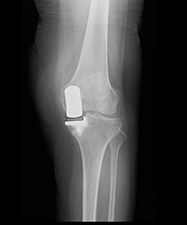

単顆置換術後のX線

一方で、大腿骨の骨壊死やまだ末期手前の変形性関節症など、そこまで変形は強くないものの、保存治療では良くならない患者さんには、痛みのある内側だけを手術する「単顆置換術」を行います。この方法では筋肉へのダメージが全置換に比べてかなり少なく、その分術後の痛みや回復が早いというメリットがあります。ただし、O脚変形が強い人や関節リウマチのような炎症による膝の変形には行えず、医師による適切な判断が必要です。